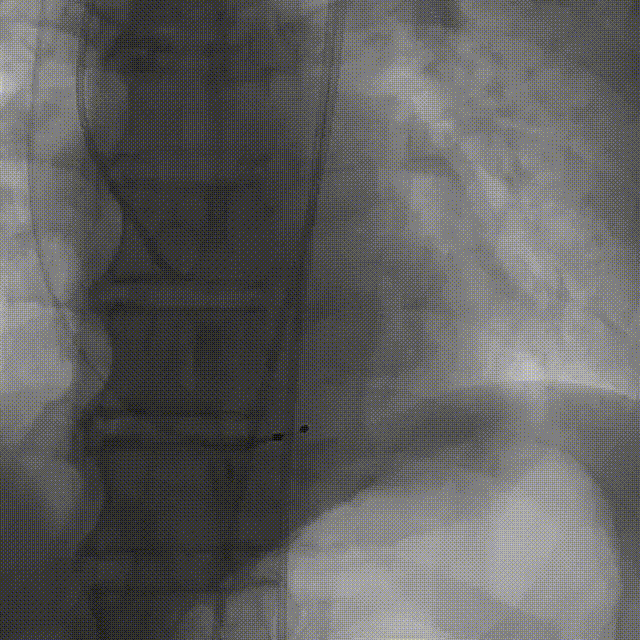

袁祖贻院长 西安交通大学第一附属医院 创新见证中国领跑,数据积累筑牢临床效果 韩克教授 西安交通大学第一附属医院 干瓣技术革新赋能特殊人群治疗,“量体裁衣”筑牢安全防线 患者病史 主诉与现病史:5年前因"血友病,血尿”就诊于当地医院,住院期间行心动超声提示主动脉瓣及二叶瓣畸形,无胸闷气短,无胸痛,咳嗽咳痰,无头晕,恶心呕吐等不适。未予以干预,后规律复查心超,3周前复查心超提示:主动脉瓣二瓣化畸形并重度狭窄,升主动脉内径明显增宽。 既往史:确诊血友病A型40年 术前超声提示:先天性主动脉瓣二叶式畸形,主动脉瓣中度狭窄,升主动脉增宽,左室舒张功能减低,EF73% 术前CT:Type0型二叶瓣,瓣叶增厚无钙化,主动脉瓣环径24.1mm,LVOT23.9mm;双侧冠脉开口高度可,窦部空间可,STJ、升主动脉内径可;预估冠脉低风险;主动脉水平夹角37.1°,主动脉弓角、弓距可;左室内径可;外周入路无明显迂曲,无钙化;双侧股动脉内径可,右侧股动脉低分叉。 手术策略 推荐右侧股动脉为主入路,左侧股动脉为辅入路。右股分叉上方1mm穿刺;仅舒张期时相,需根据球扩结果评估瓣膜尺寸,推荐使用18mm球囊进行预扩;预装AV26瓣膜。 手术过程 在右股动脉穿刺建立通路后,顺利送入大鞘。18mm球囊预扩后评估无腰无漏,后将Prostyle A® AV26瓣膜精准释放于目标位置,术后即刻造影显示无明显反流,无瓣周漏,平均跨瓣压差由术前的100mmHg降至2mmHg,患者血流动力学显著改善,术后超声证实瓣膜启闭良好。 主动脉根部造影 18球囊预扩 定位 稳定释放后脱钩 最终造影形态位置良好 外周血管造影,无血管并发症 术后超声显示无生物瓣位置固定瓣膜功能正常,无瓣周漏。 Prostyle A®预装干瓣——助力临床最优化解决方案 流入端桶状设计:流入端桶状的设计,锚定迅速,有效减少释放步骤,提升植入稳定性; 平衡的收腰设计:二叶瓣患者对瓣膜径向支撑力提出更高要求,Prostyle A®均衡的收腰设计可更好适应二叶瓣解剖,保证了EOA,有效降低了循环崩溃风险,提高瓣膜的耐久性; 预装干瓣 便捷顺安:金仕生物专利抗钙化技术运用纳米技术去除组织内的细胞碎片和磷脂,封闭游离醛基,从根本上阻断了瓣膜钙化的多项因素,显著提升了瓣膜的耐久性;同时,相比较传统戊二醛保存方式,干式存储最大限度的保留心包的亲水亲油平衡,还原组织天然曲柔性,进一步保障了瓣叶开合,保证长期耐久性。 专家简介 袁祖贻 西安交通大学第一附属医院(点击查看专家详细简历) 韩克 西安交通大学第一附属医院(点击查看专家详细简历) · END ·